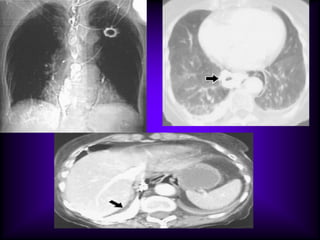

Fungous Ball

Long standing cavity

Containing round density (A)

Mobile density

Adjacent pleural reaction (B) - characteristic of aspergilloma